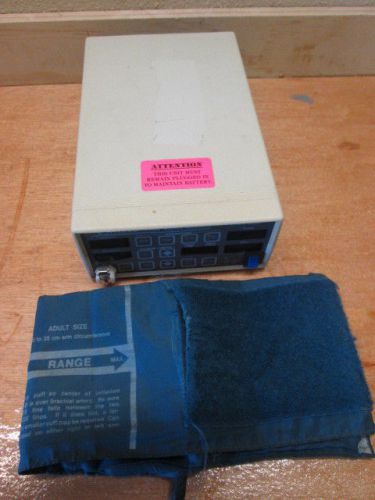

NIBP HOSE CRITIKON DINAMAP 8100 8100T 9300XL 1846

Critikon Dinamap Model 1255 Research Monitor